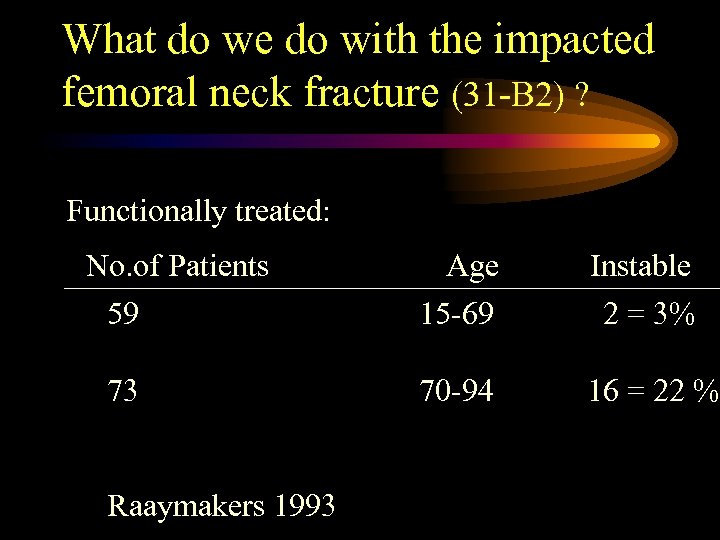

What do we do with the impacted femoral neck fracture (31 -B 2) ? Functionally treated: No. of Patients 59 73 Raaymakers 1993 Age 15 -69 Instable 2 = 3% 70 -94 16 = 22 %

What do we do with the impacted femoral neck fracture (31 -B 2) ? Functionally treated: No. of Patients 59 73 Raaymakers 1993 Age 15 -69 Instable 2 = 3% 70 -94 16 = 22 %